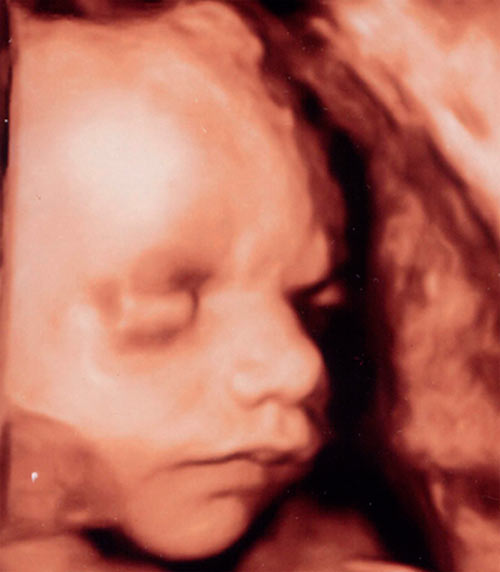

Ultrasound photo on the 29th week: